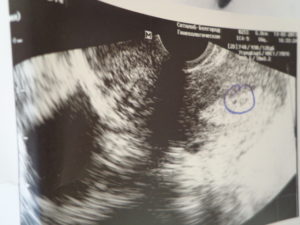

- УЗИ органов малого таза, дает ответ с высокой точностью;

- на УЗИ (надежный результат);

Информативным методом в диагностике является УЗИ. Процедура позволяет определить, в каком состоянии находятся яичники, формируются ли фолликулы, присутствует ли жидкость в позадиматочном пространстве.